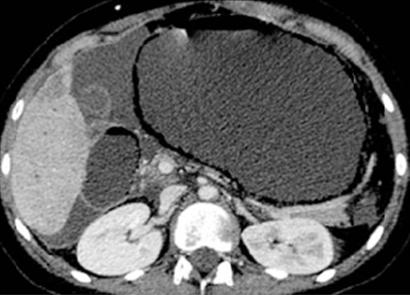

Image TDM en coupe axiale et

dans la paroi de estomac ( coupe TDM coronale ) |

Image radiologique TDM

peritoneale ( peritonite ) |